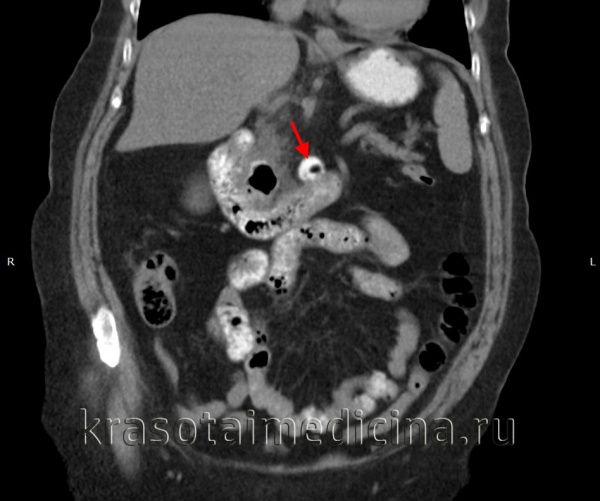

Методы диагностики. Дивертикулез легко выявляется при иригоскопии и при компьютерной томографии (КТ) с контрастированием.

Иригоскопия с двойным контрастированием выявляет дивертикулы (см. рис. 1), любые стриктуры, и может также помочь в обнаружении свищей (см. рис. 2).

КТ ОБП. Дивертикул горизонтальной части 12-перстной кишки, заполненный частично контрастом, частично – газом.